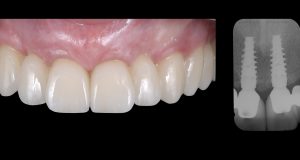

Muco-integration of dental implants for long-term tissue health and stability